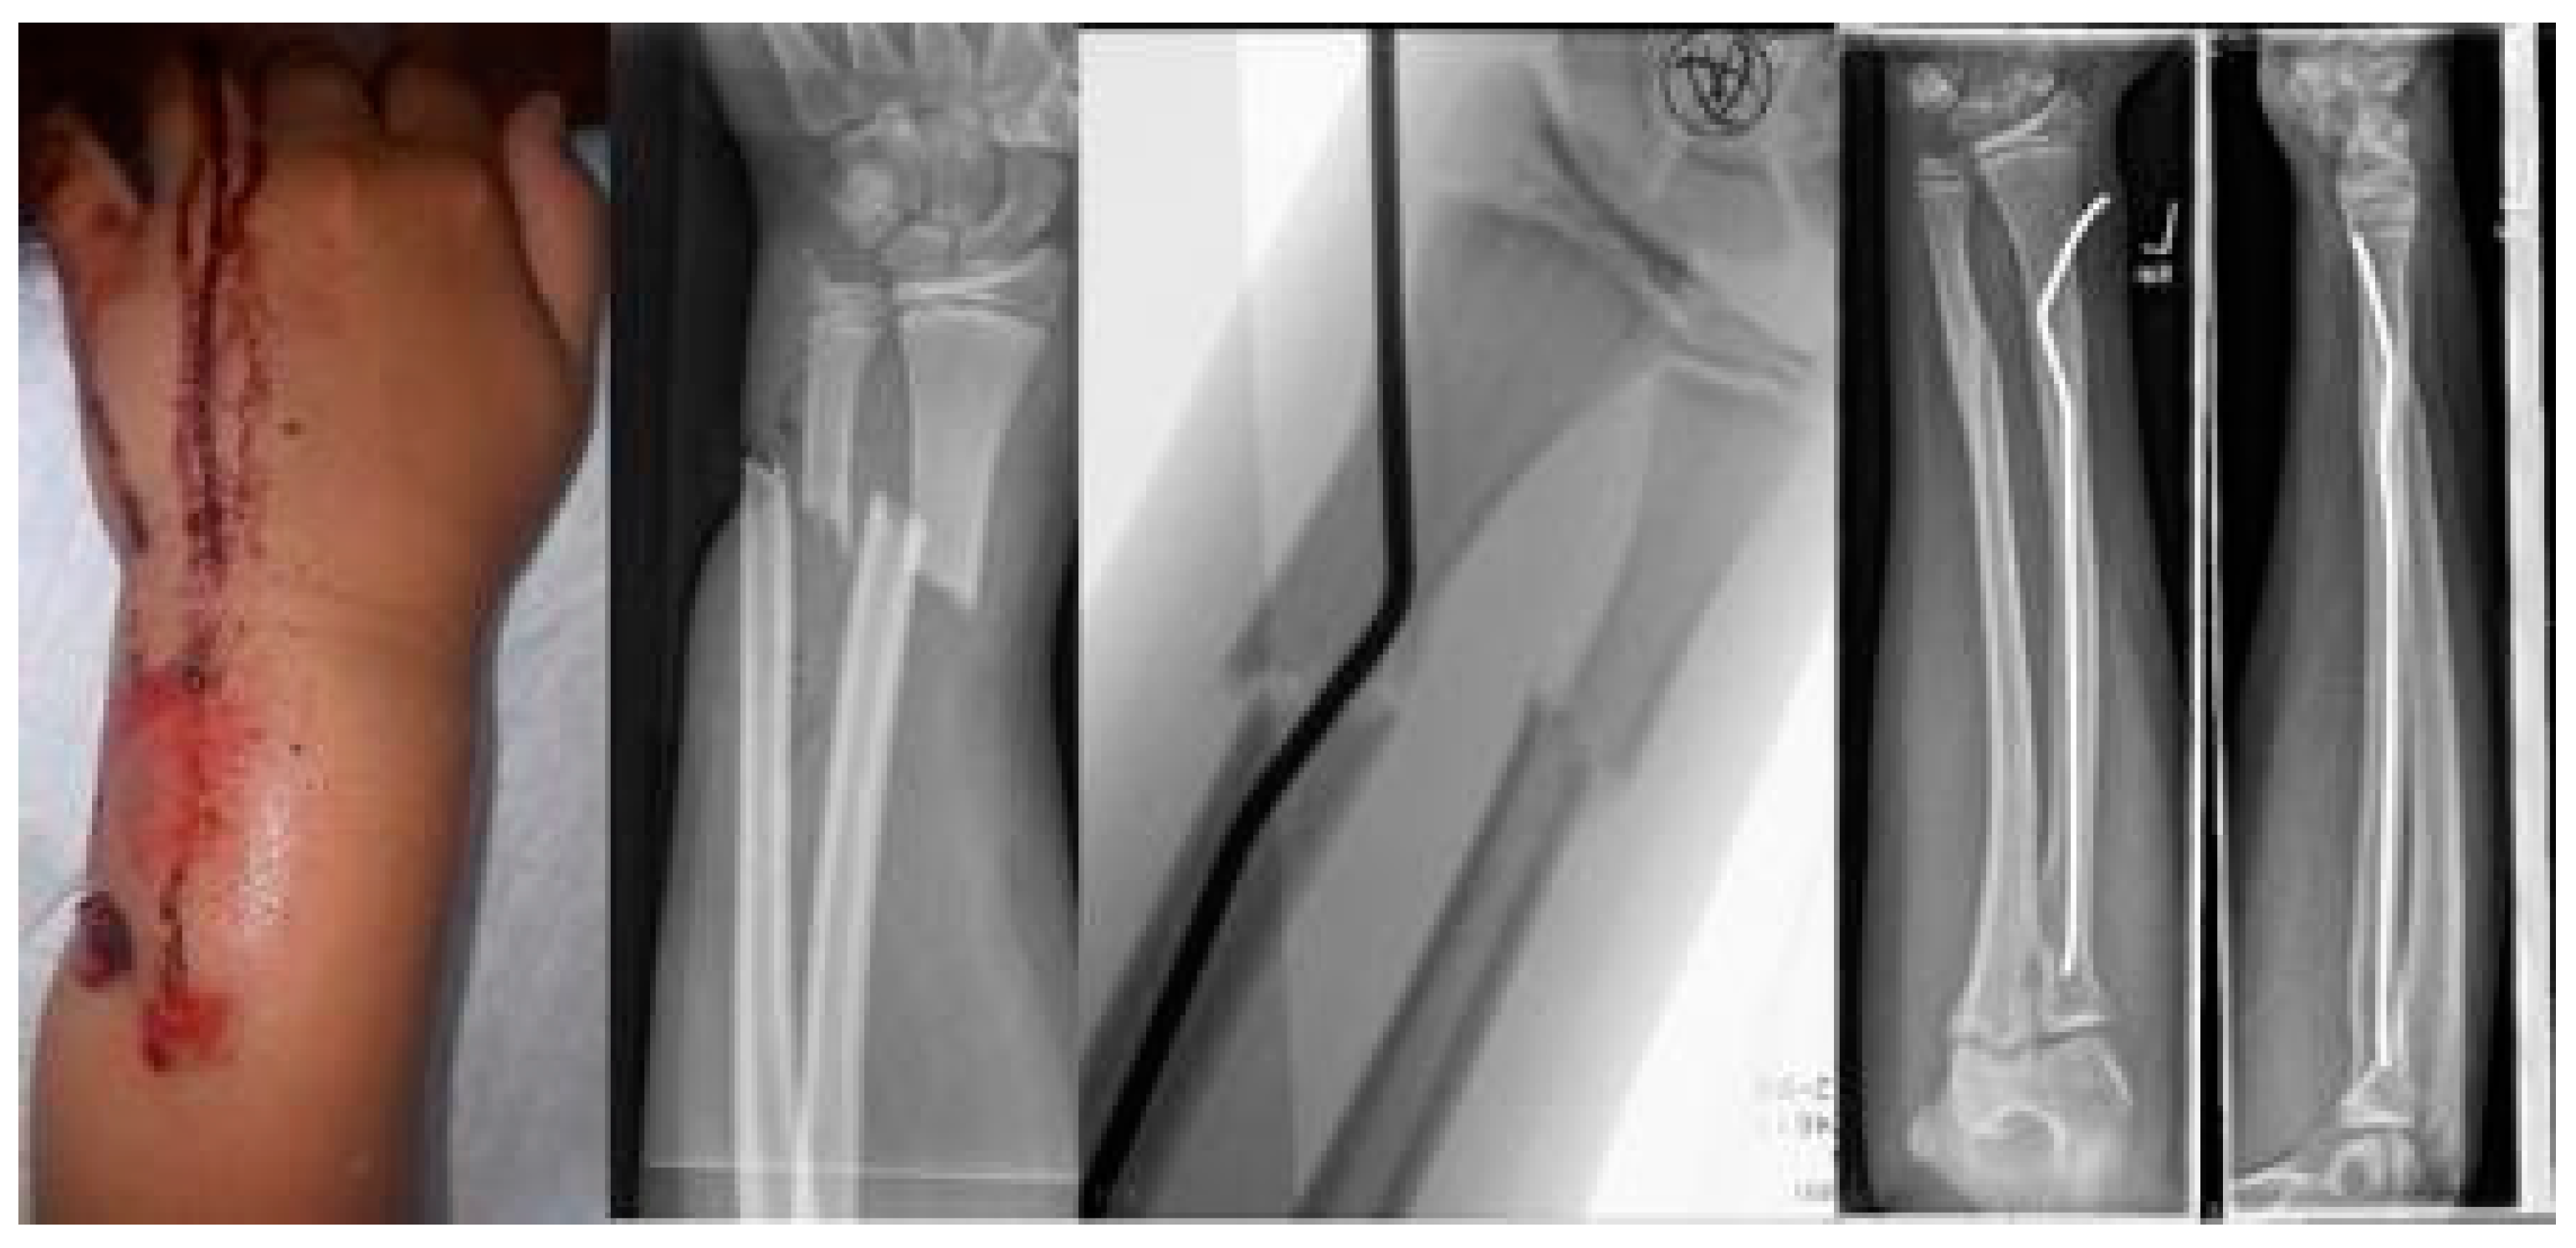

Scheme 1. Closed reduction 4 weeks after insufficient k-wire osteosynthesis with a bend instead of the distal kink as a variant of this procedure.

The youngest patient was a two-year old boy, who presented with an unacceptable secondary displacement two weeks after trauma and, thus, this fracture became a rare indication for osteosynthesis in this age group (Scheme 2). The eldest was 17 years of age and did not show epiphyseal plates anymore (Scheme 3). This patient, however, suffered a new trauma 3 weeks later and underwent a redo-procedure in another hospital and, thus, was lost to follow-up. We even treated an open forearm fracture (on the ulnar side) with this technique (Scheme 4), leaving the fracture of the ulna to spontaneous healing and correction. This was because the risk of osteomyelitis due to intramedullary nailing of the open ulnar fracture to achieve a “nice X-ray” was estimated to be much higher than the risk of a remaining misalignment. Even a redo-procedure of a fracture that we had seen for the first time 4 weeks after an unacceptable K-wire osteosynthesis was successful, this time using a modification of the technique with a bend, rather than a kink distal to the fracture. Please note that the pre-bent nail pushed the 4-week-old fracture into a correct position without open reduction (Scheme 4). Last but not least, curiously, we saw one patient who suffered identical fractures in both arms, so we could perform the procedure twice in one operation (Scheme 5).